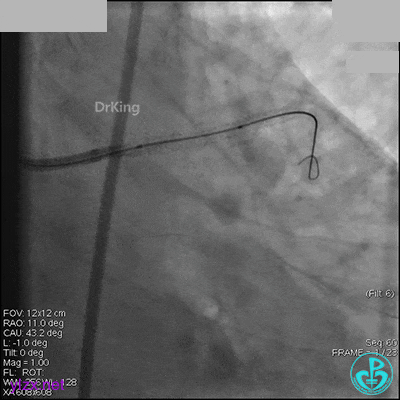

1周后再次上台,右冠脉3级血流,3段局限性严重狭窄,内膜模糊,应该是上次操作夹层遗留下的血肿。

先处理前降支开口严重狭窄并顺利植入前降支到左主干支架。